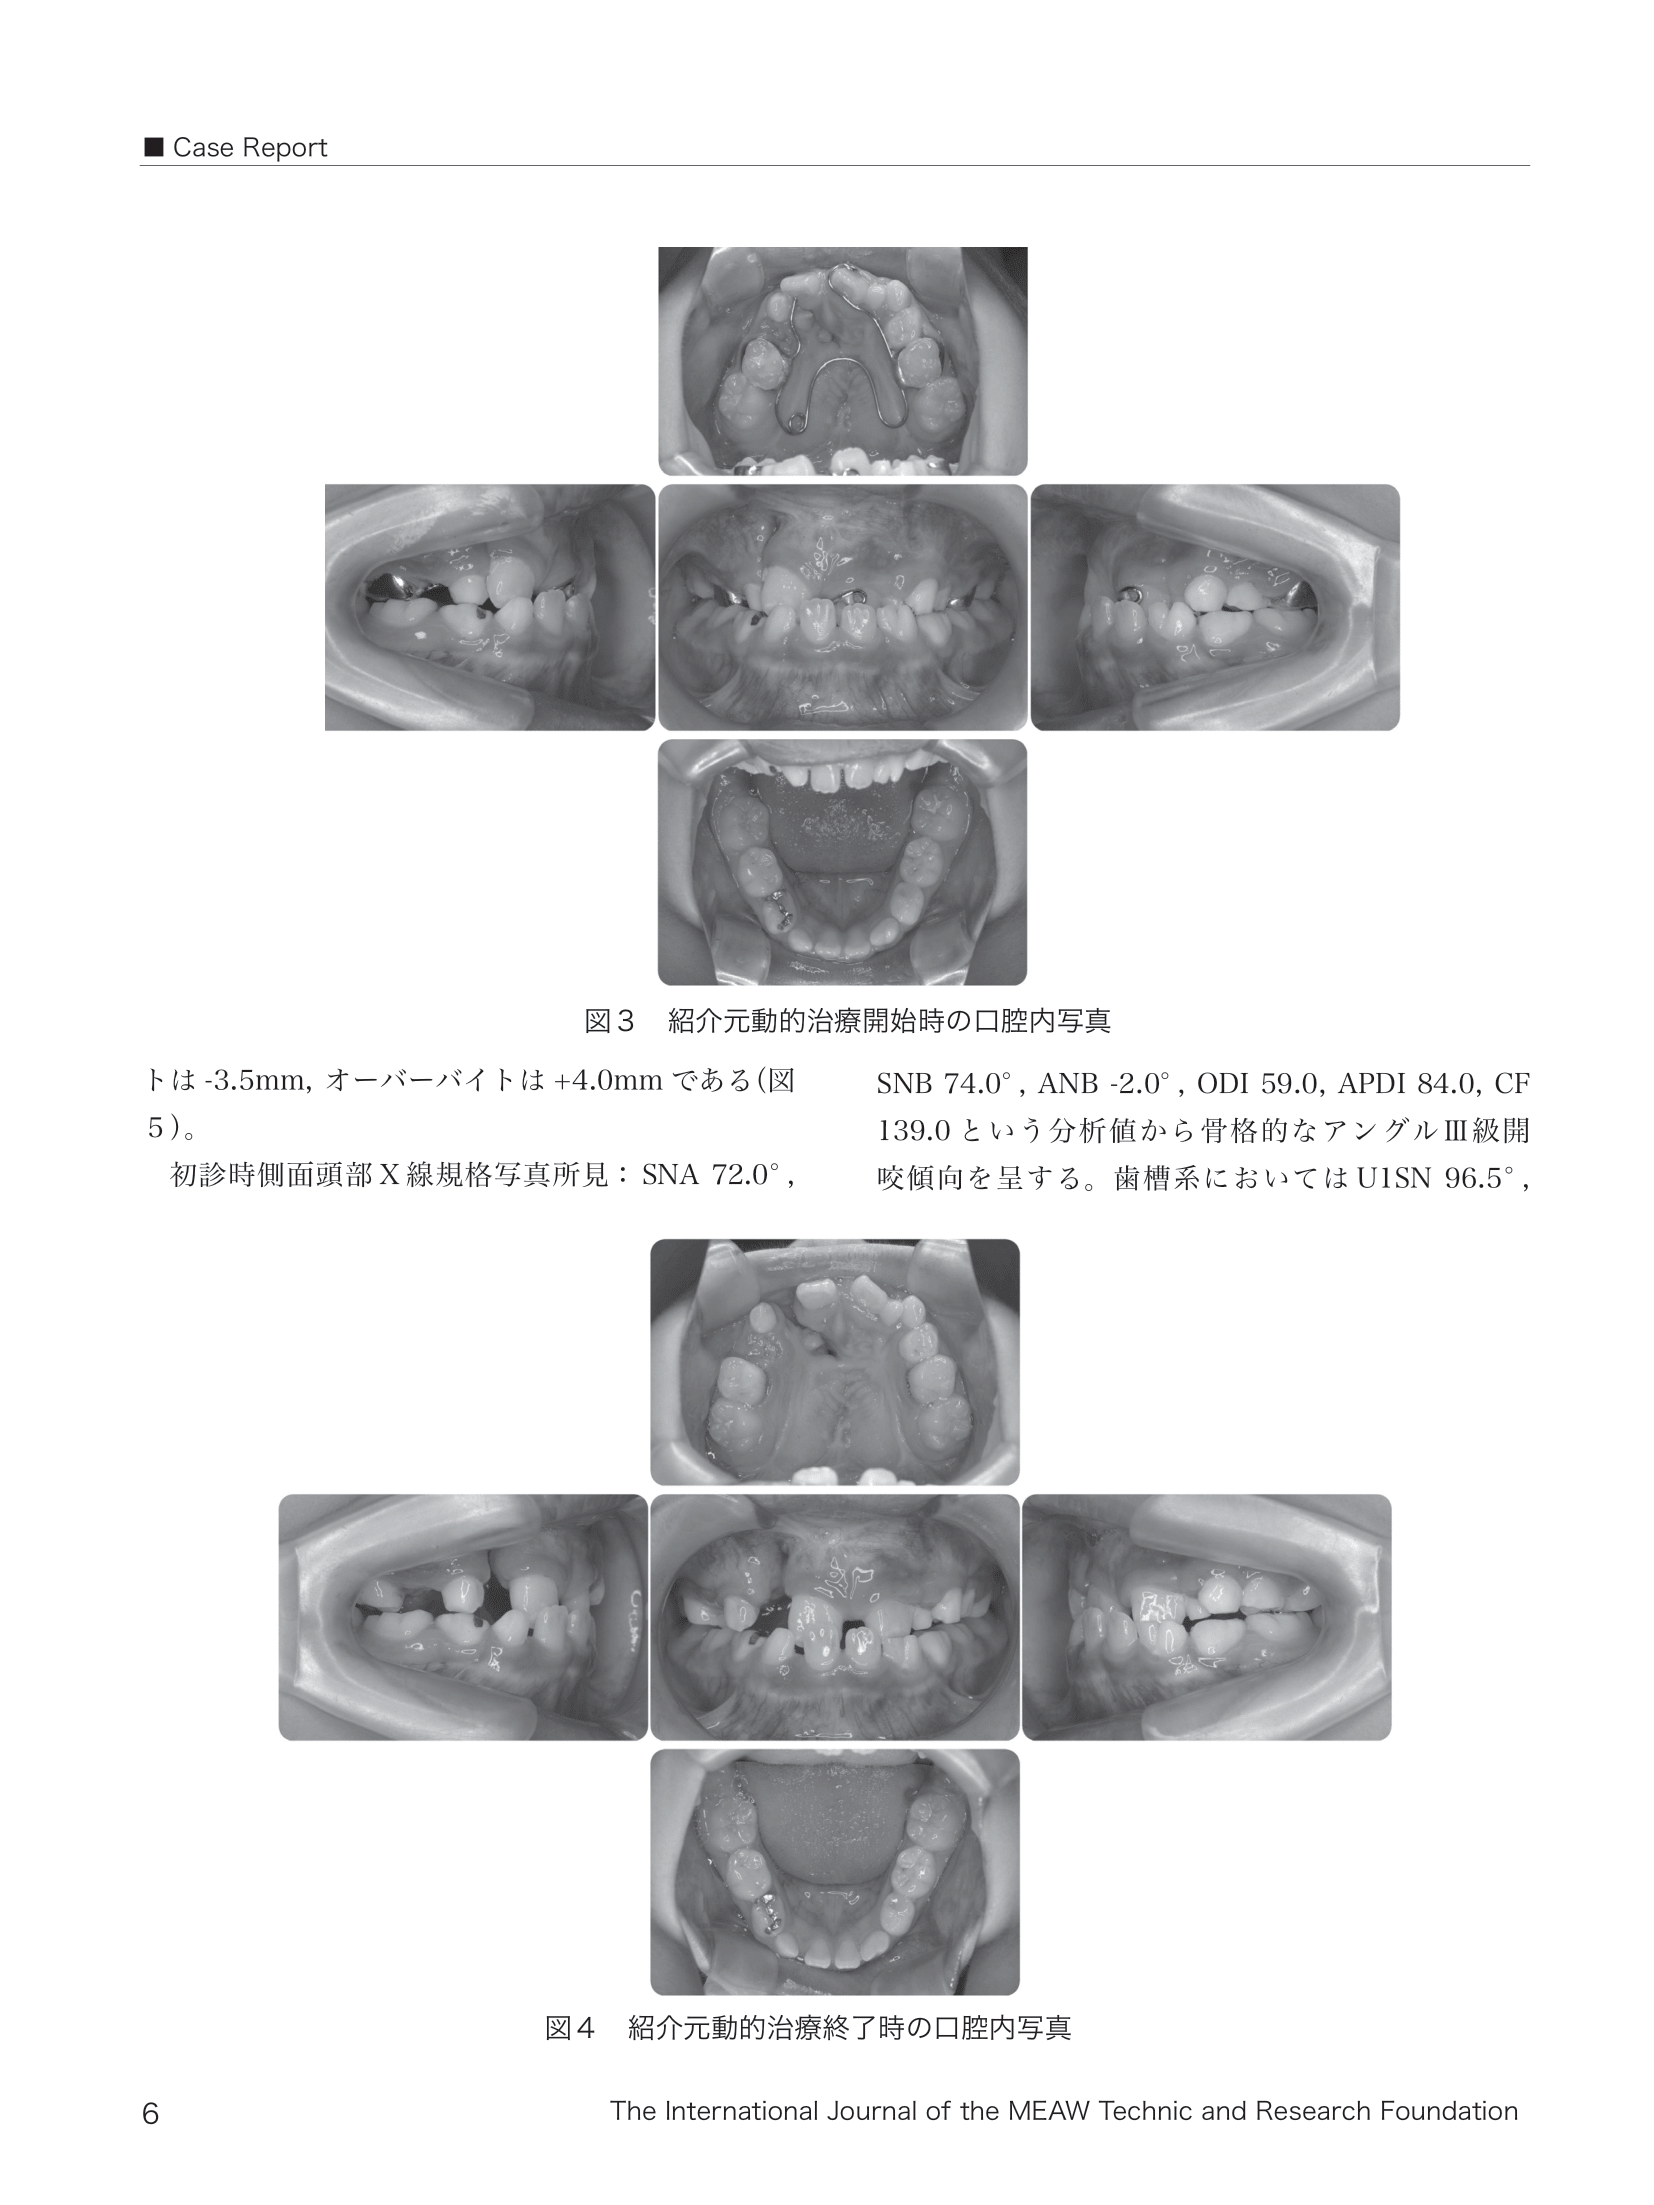

MEAW‚π—p‚’‚ΔŽ‘—Γ‚πs‚Α‚½ζ“VŒ‡”@Ž•‚¨‚ζ‚ѐOŠ{ŒϋŠW—τ‚π”Ί‚€‰ΊŠ{‘O“ˏǗαi˜a“‡j